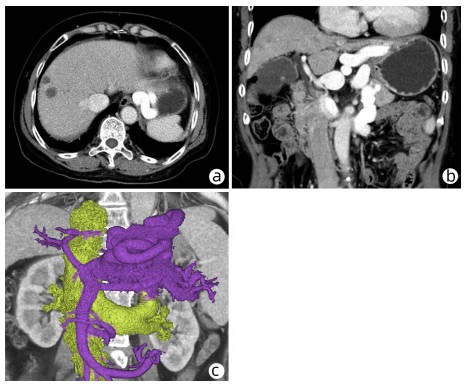

巨大肝血管瘤伴弥漫性动脉-门静脉瘘1例报告

周帮健, 杨俊, 印于, 朱晓黎, 倪才方, 王万胜

2023, 39(3): 640-643. DOI: 10.3969/j.issn.1001-5256.2023.03.025

摘要(1061) HTML (229) PDF (3500KB)(116)

摘要: